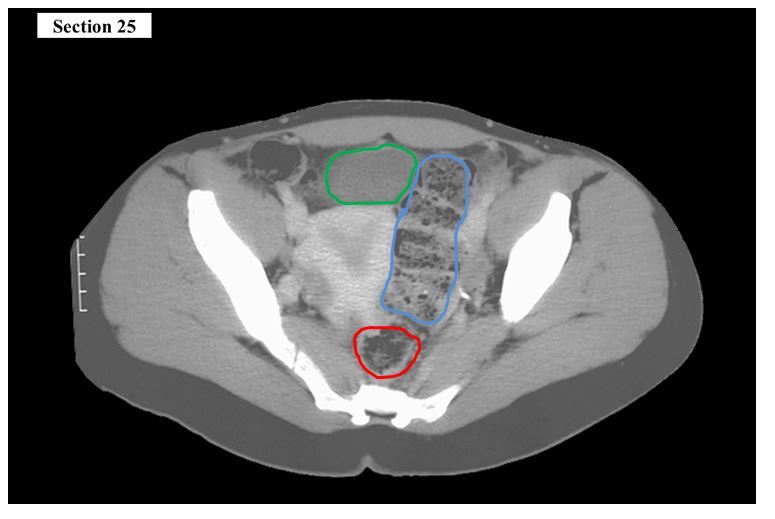

The red structure is the ___ and the blue structure is the ___

A

right ureter

left ureter